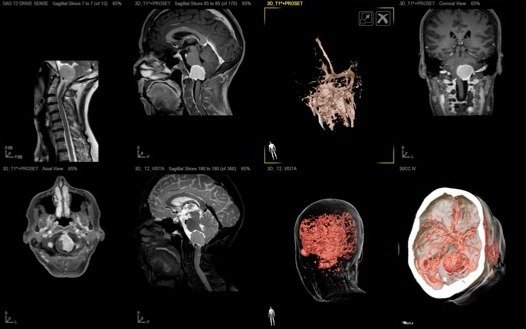

A: PRE-SURGICAL IMAGES

MRi 3T CT-scan